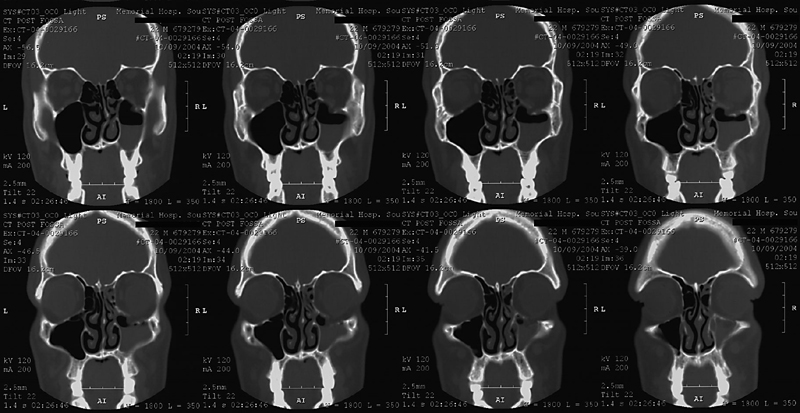

Orbital Floor Fracture

This CT shows what happens when the face of a medical student in the class of 2008 meets a hard object. Note the fracture of the orbital floor, with herniation of orbital contents into the maxillary sinus and accumulation of blood within the sinus.